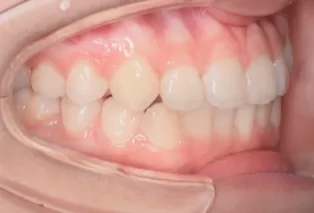

Photos intra-orales après traitement